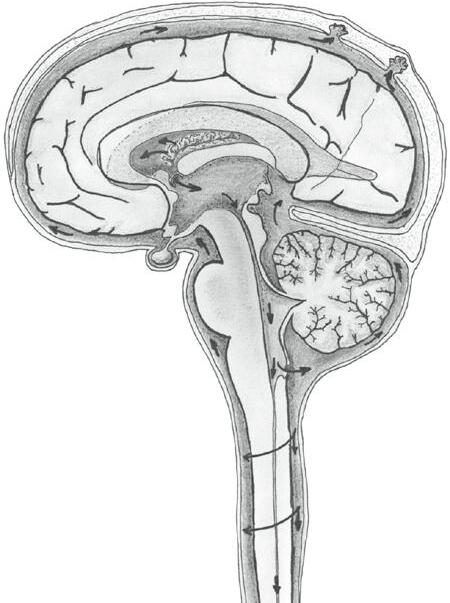

Mozkomíšní mok je produkován v choroidálním plexu (plexus choroideus), který nacházíme v postranních mozkových komorách (I. a II. mozkové komoře). Tyto komory leží v hloubi mozkových polokoulí. Drobnými otvory mozkomíšní mok proudí do nepárové III. komory mozkové ležící na úrovni mezimozku (respektive mezi dvěma talamy).

Sylviovým mokovodem (aquaeductus cerebri – Sylvii) postupuje mozkomíšní mok dále do IV. komory mozkové na horní ploše mozkového kmene. Odtud se dostává do úzkého centrálního míšního kanálu (canalis centralis), který sestupuje středem hřbetní míchy.

Pohled zepředu

Pohled z boku

postranní komory (I. a II. komora)

Obr. 2.23 A Komorový systém mozku

III. komora

Sylviův kanál

IV. komora

centrální kanál míchy

subarachnoidální prostor tvrdá plena

koncový mozek

choroidální plexus

hypotalamus

hypofýza

mozkový kmen střední mozek

Varolův most prodloužená mícha

páteřní mícha

Obr. 2.23 B Schéma cirkulace mozkomíšního moku

žilní splav

arachnoidální klky

postranní komora mozková

III. komora mozková

Sylviův mozkovod

mozeček

IV . komora mozková

subarachnoidální prostor

centrální míšní kanál

Třemi drobnými otvůrky na stropě IV. komory vstupuje mozkomíšní mok do zmíněného subarachnoidálního prostoru, ve kterém omývá celý mozek a hřbetní míchu.

Poznámka: Nové výzkumy dokládají, že proudění mozkomíšního moku je mnohem složitější a jeho funkce jsou daleko komplexnější, než jsme se dříve domnívali. Ukazuje se například, že se mozkomíšní mok podílí na odstraňování odpadních látek z mozkové tkáně.

Mozkomíšní mok vzniká permanentně, jeho proudění mozkovým komorovým systémem usnadňuje pohyb výběžků ependymových buněk, které mozkový komorový systém vystýlají. Přebytky mozkomíšního moku se vstřebávají do žilní krve prostřednictvím arachnoidálních klků neboli Pachionských [čti pačijonských] granulací. Jedná se o výchlipky pavučnice, které v temenní oblasti ční do nitra žilních splavů (viz dále).